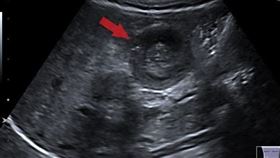

嚇!五旬婦腹痛不止 竟是避孕器穿透子宮

55歲的張女士日前因腹痛1個多月,本以為是腸胃症狀,...